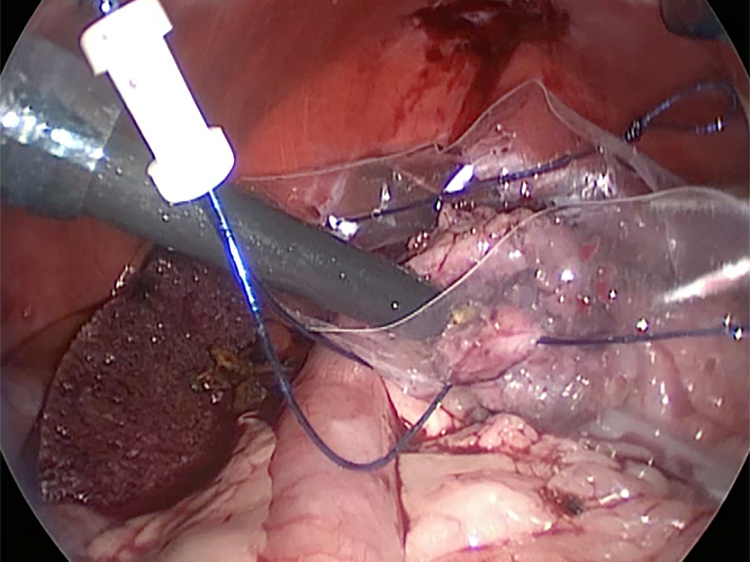

他院より紹介。胆嚢炎がひどく繰り返す嘔吐がありました。 腹膜と一部横隔膜に胆嚢ががっちりと癒着していました。 体重が2kgと体も小さかったのですが、飼い主さんの希望もあり、腹腔鏡下で手術を実施することになりました。

丁寧に丁寧に出血をコントロールしながら少しずつ手術をすすめていきます。

癒着(矢印)がひどく胆嚢を確認することができませんでした。 このように癒着しているときはギリギリで剥がすとひどく出血をおこすことがあるので無理にはがそうとしないで、脂肪の血管に注意しながら脂肪ごと剥がしていきます。

胆嚢は分厚くなり周りには脂肪が張り付いていました。手術をして元気になりました。

胆嚢(矢印)の取り囲むように肝臓や腸が癒着していました。肝臓の表面はボコボコしています。